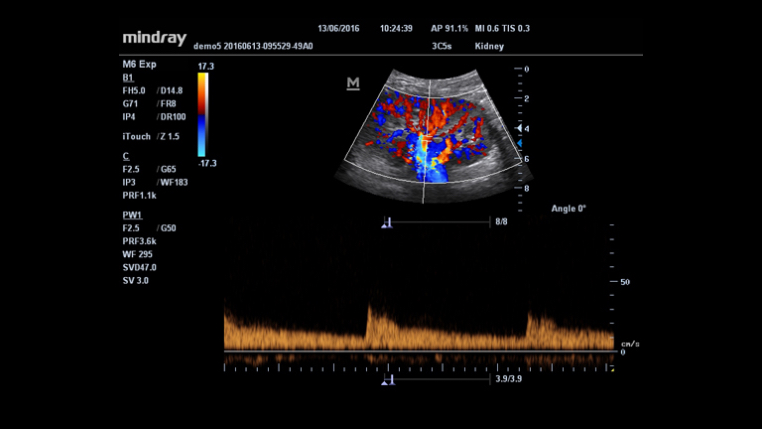

- 3C5s

HR Flow™

Innowacyjna technologia dla uzyskania lepszej wizualizacji małych naczyń krwionośnych i skomplikowanych przepływów, oparta na ekskluzywnym algorytmie przetwarzania Firmy Mindray.